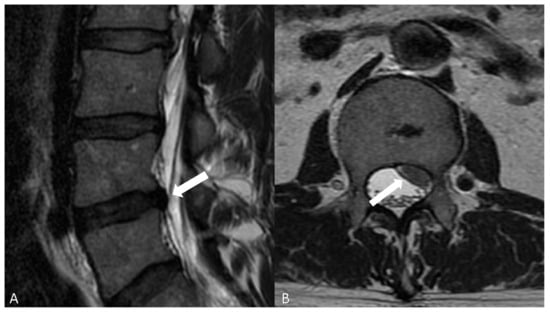

- Modic classification [16] is a classification for vertebral end plates and adjacent vertebral bodies MRI signal modifications secondary to disc inflammation and degenerative disc disease. Modic type 1 refers to decreased signal intensity on T1-weighted images and increased signal intensity on T2-weighted images. Such modifications may be chronic or acute and reflect the penetration of the end plate by fibrovascular tissue, inflammatory changes, and edema. Modic type II refers to increased signal intensity on T1-weighted images and isointense or increased signal intensity on T2-weighted images, indicating replacement of normal bone marrow by fat. Modic type III refers to decreased signal intensity on both T1- and T2-weighted images, indicating reactive osteosclerosis [55] (Figure 4).